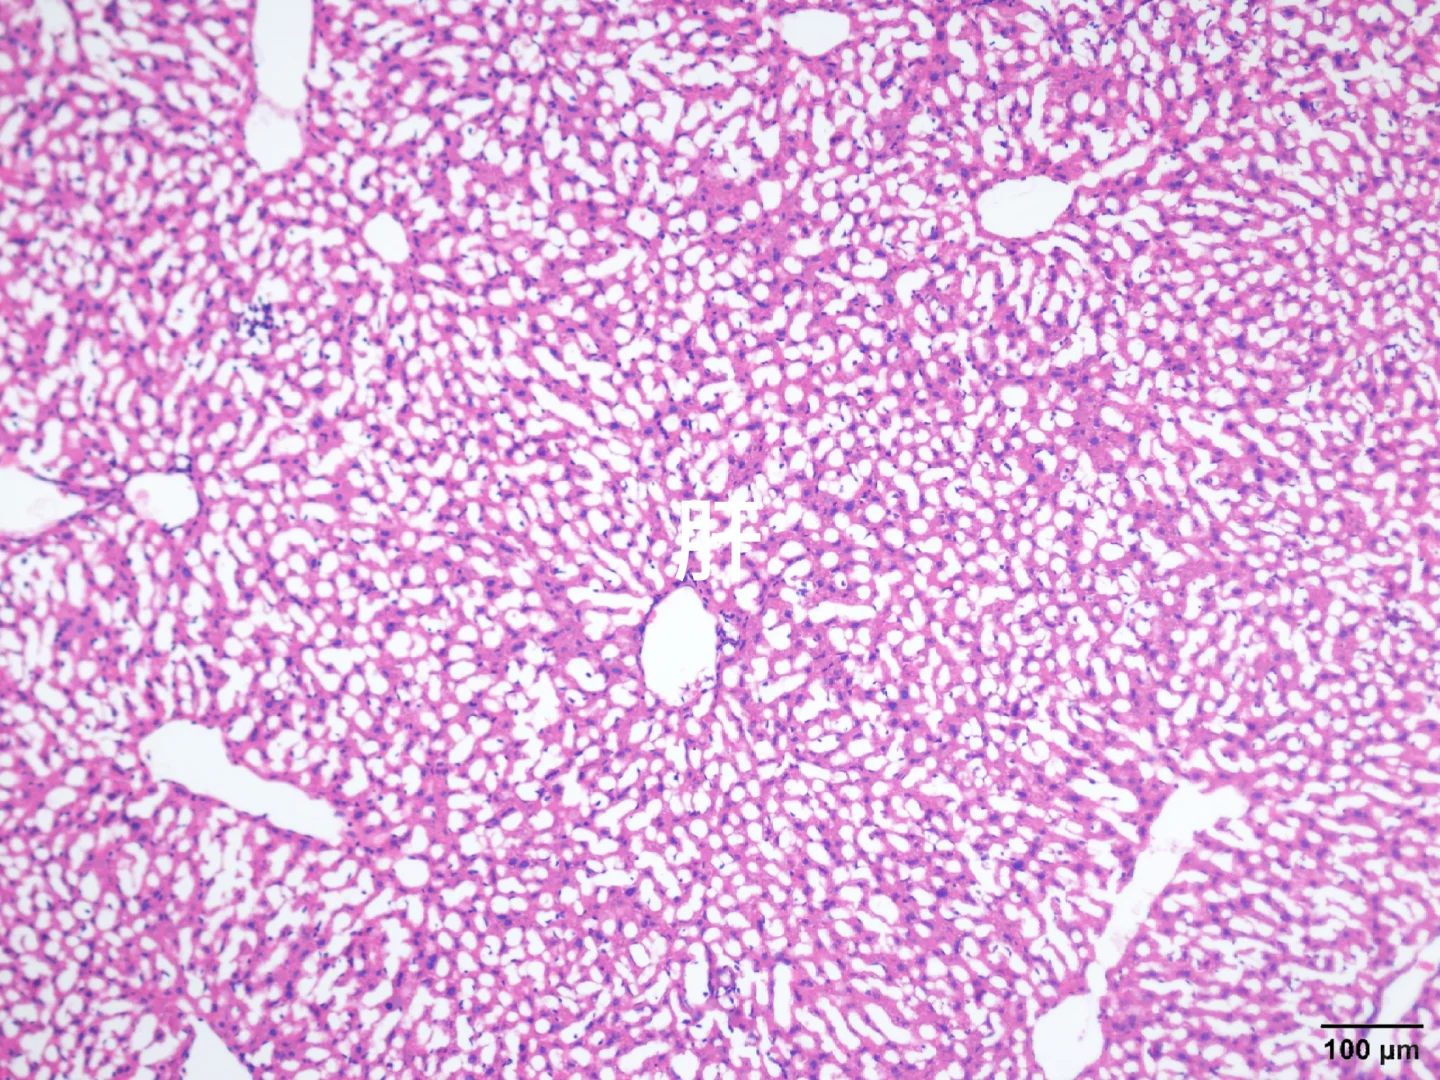

心肝脾肺肾肿瘤HE染色

由于我取了组织后用多聚甲醛固定,然后不小心放-80°一天,后面又放回四度,有没有大神帮忙看看能不能用!